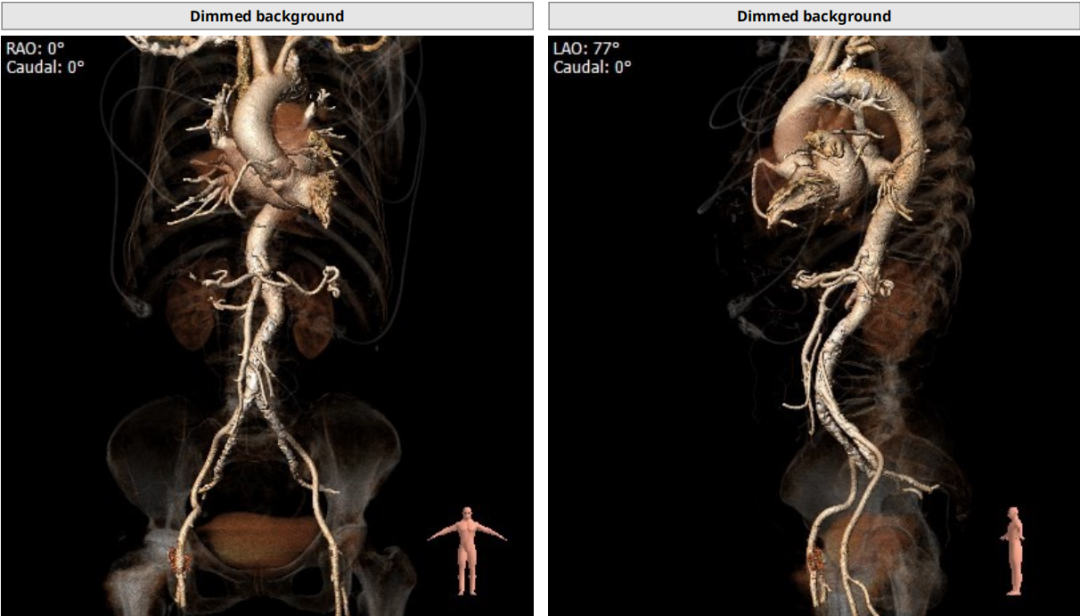

术前CT评估:

瓣环平均直径:25.2mm,左室流出道平均直径:25.5mm;

升主动脉(未见)明显扩张,心脏角度:47°;

左冠高度:12.1mm,右冠高度:16.1mm。

Annulus:25.2mm

LVOT:25.5mm

Sinus:22.1mm*32.6mm STJ:30.3mm

升主:34mm*34.7mm 主动脉成角:47°

钙化积分:272

手术策略

患者主动脉瓣呈功能性型二叶瓣,轻度钙化,法式窦结构不大,双冠高度可,升主动脉未见明显增宽,心脏角度约47°,心肌肥厚,主动脉弓部走形平缓。